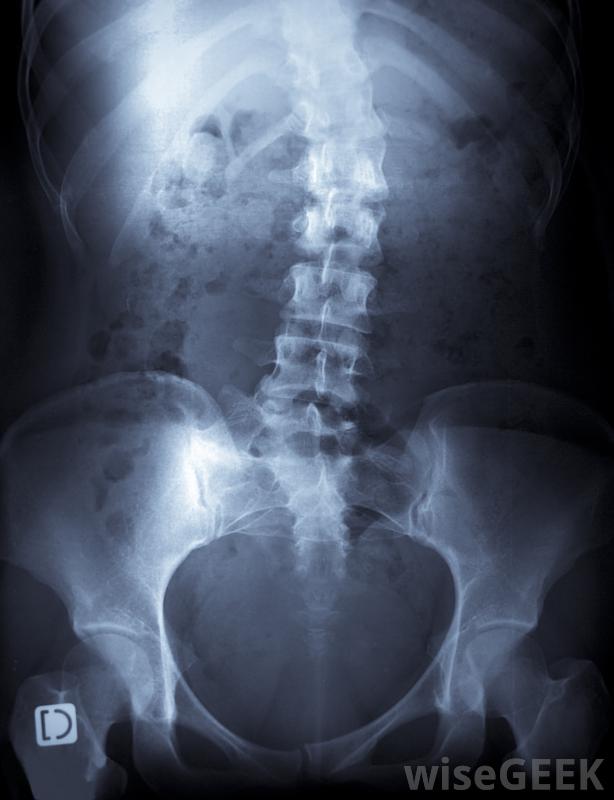

脊柱側凸是脊柱側彎的一種骨骼畸形。脊柱側凸的最佳治療方法取決于許多因素,包括彎曲的嚴重程度和位置,畸形的根本原因,以及患者的年齡。仍在成長中的兒童和青少年通常安裝有有助于使脊柱更直的支架。患有嚴重脊柱側凸的成人和年輕人通常需要進行手術以減輕疼痛并防止病情惡化。持續的物理治療和頻繁的檢查可以幫助他們確保脊柱側凸的治療成功。脊柱側凸引起的脊柱彎曲的嚴重程度是決定最佳治療方法的一個因素大多數脊柱側凸的病例很容易識別,即使是輕微的脊柱彎曲也會導致肩部或臀部不均勻。人們經常會感到慢性背痛和疲勞,尤其是長時間坐著或站著之后,中度到重度曲線的人可能走路步態笨拙,難以進行體育活動。當個人或其子女出現癥狀時,安排醫生的預約是很重要的;當脊柱側凸的早期發現時,治療是最有效的。脊柱側凸可以戴上背帶醫生可以檢查病人的身體癥狀,摸摸脊柱和周圍組織,并給背部拍x光片。為了做出正確的診斷,醫生可能會進行額外的檢查,以檢查潛在的病因。有些脊柱側凸是先天性缺陷、神經肌肉疾病和關節炎造成的不過,這種情況通常是特發性的,一些嬰兒先天性和特發性脊柱側凸的病例在出生后的幾年內就自行糾正了。6歲以下的兒童通常不接受脊柱側凸的治療,除非他們的曲線非常嚴重。對于年齡較大的兒童和青少年來說,每天戴幾小時特制的背帶被認為是最好的治療方法。就像牙齒上戴的牙套一樣,背托施加的壓力很小,可以逐漸拉直脊柱。在骨骼靜止的時候戴上支架在發育過程中,椎骨更容易長成一條直線。對于成人、有嚴重曲線的兒童,手術通常被認為是脊柱側凸的最佳治療方法,以及患有神經肌肉疾病的所有年齡段的人。一組熟練的外科醫生可以進行一項非常精細的手術,將椎骨融合在一起,從而防止脊柱彎曲惡化。手術通常對緩解疼痛和其他癥狀非常有效,雖然完全糾正這種情況的手術很少見,但人們一生中仍可能會經歷背痛通過加強鍛煉和定期與醫生會面,患者通常可以學會應對自己的狀況并享受定期活動。物理療法可能有助于治療成人脊柱側凸。